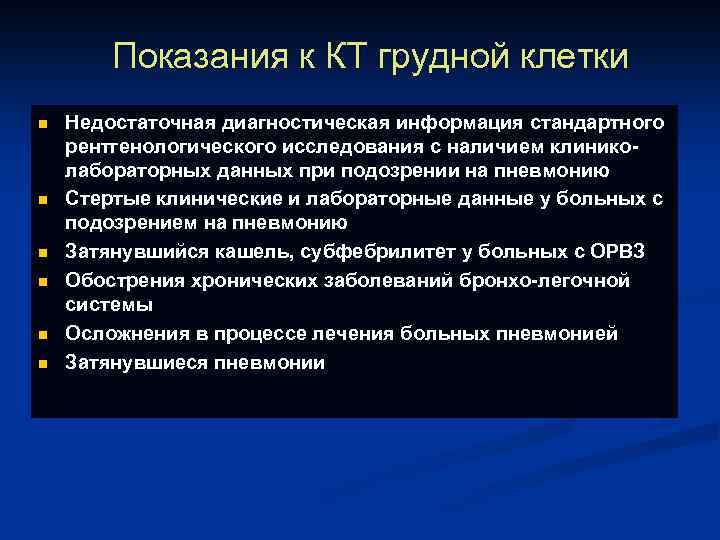

Показания к КТ грудной клетки n n n Недостаточная диагностическая информация стандартного рентгенологического исследования с наличием клиниколабораторных данных при подозрении на пневмонию Стертые клинические и лабораторные данные у больных с подозрением на пневмонию Затянувшийся кашель, субфебрилитет у больных с ОРВЗ Обострения хронических заболеваний бронхо-легочной системы Осложнения в процессе лечения больных пневмонией Затянувшиеся пневмонии